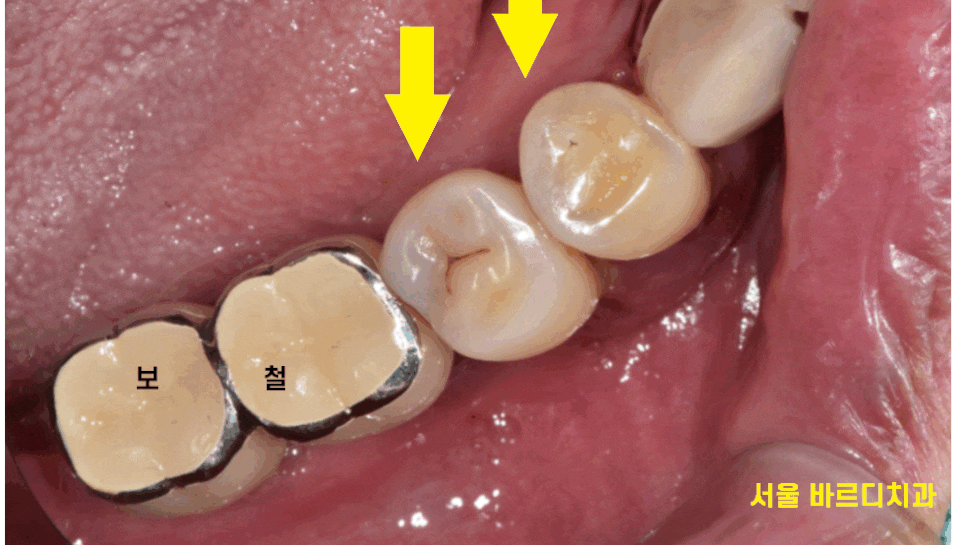

전악 임플란트를 하셨고

남아있는 내 치아는 딱 2개

오른쪽 아래 작은 어금니만 본인 치아셨습니다.

보철 치아와 비교하였을 때

자연치아는 티가 나죠~?

아주 작은 충치가 있긴 하였지만

이정도는 관리만 잘해도 되는 수준